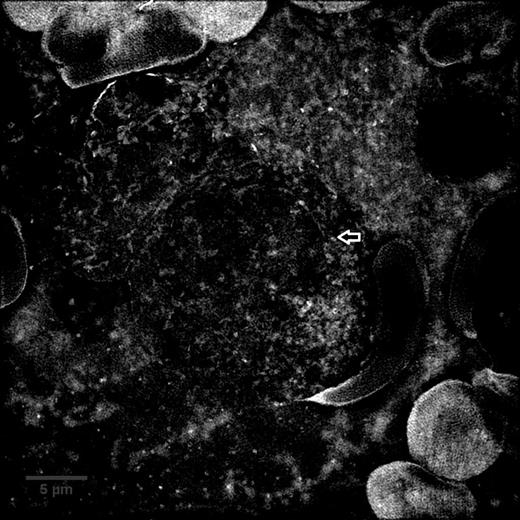

Granular B-ALL bone marrow aspirate sample imaged with SIM and converted to a maximum intensity Z projection, arrow indicates a granule